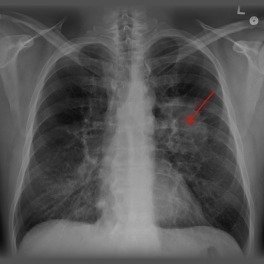

Bristol Myers Squipp firması tarafından üretilen nivolumab içerikli OPDIVO isimli ilaç geçen yıl melanoma cilt kanserinde Amerikan ilaç ve gıda kurumu (FDA) tarafından onaylanmıştı. Aynı ilaç ile ilgili Akciğer kanseri için bilimsel çalışmalar devam etmekte iken, sonuçların çok başarılı olması üzerine FDA bu yılın başında hızlandırılmış onay prosedürü ile bu hastalarda kullanımını onayladı. İlaç Avrupada da hızlandırılmış onaya tabi tutuldu. Birçok ülke ilacı hızla onay sürecine soktu. Akciğer kanserinin bir türü olan skuamöz hücreli kanser tedavisinde yıllardır yeni bir gelişme olmamıştı ve bu hastalar mevcut kemoterapi tedavilerine cevap vermediklerinde tedavisiz kalıyorlardı. Bu ilacın geliştirilmiş olması belirttiğim hasta grubu için yeni bir tedavi olanağı sağladı. Kemoterapiden farklı olarak immunoterapi yöntemi olan bu ilacın tek tek başvuran hastalarda kullanılmasına izin veren Sağlık Bakanlığı, ilacın ülkemize toplu ithal edilerek hastanelerde yaygın olarak kullanılmasını henüz sağlamadı. Sosyal Güvenlik Kurumu da bu ilaç için ödeme yapmamaktadır. İlacı ithal etmek isteyen vatandaş ise vergiler ile aylık 19600 (ondokuzbinaltıyüz) dolar ödemek zorunda kalmaktadır. Bu karşılanamaz bir ücrettir. İlacın ABD fiyatının (yaklaşık 12bin dolar) çok çok üstünde olan bu fiyat vergilerle bu rakama ulaşmaktadır. Tedavisi için kendi ücretini ödemek zorunda bırakılan vatandaştan bir de fahiş vergi alınmaktadır. Kanser tedavisinde 10bin dolarlar ödenen birçok ilaç vardır (örnek: Yervoy) ancak iş akciğer kanserine gelince nedense bakanlık ve SGK yavaş hareket etmekte ve bu ilaç ile hayatı kurtulabilecek birçok Türkiye Cumhuriyeti vatandaşı tedavisiz kalmakta ve gecikilen her gün yeni canlar kaybedilmektedir. Akciğer kanseri tedavisinde çığır açan bu ilacın uygun endikasyonlarda uygun hastalara ücretsiz uygulanmasını, SGK ve bakanlık yetkililerinin duyarlı olmasını istiyorum.